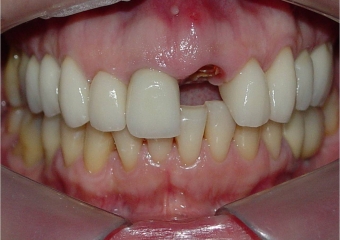

Imagem após extração e instalação de implante e prótese fixa provisória imediata